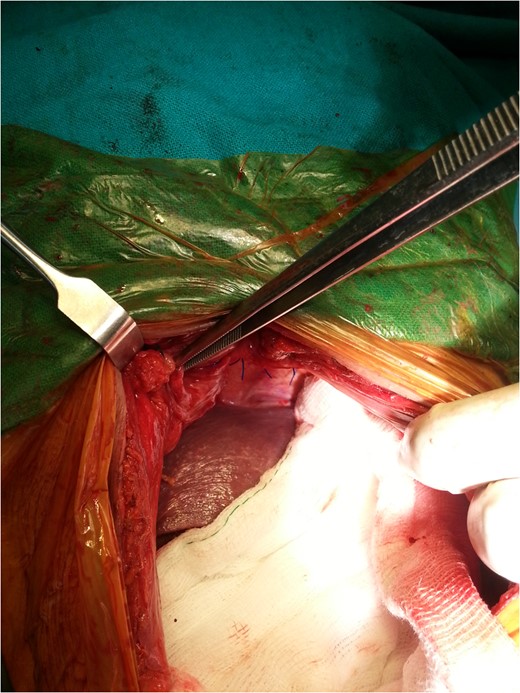

An 80-year-old man presented to our emergency room with multiple episodes of non-bilious vomiting for 4 days and not-passing stool or flatus for 2 days. He also complained of intermittent pain in the upper abdomen, which was not associated with fever, chest pain, melena or diarrhea in the recent past. However, he complained of increased cough and shortness of breath for the last 4 days on the background of a diagnosed chronic obstructive pulmonary disease. There were no similar complaints in the past. On examination, his vital parameters were normal, other than an oxygen saturation of 82% for which oxygen had to be given via face mask. His abdominal examination revealed epigastric fullness with tenderness in the epigastric and right hypochondrium. There was no evidence of peritonitis. Laboratory investigations revealed hypokalemia (3.1 mEq/l) with other parameters being normal. On the chest X-ray obtained, we saw air–fluid levels in the right thoracic cavity (Fig. 1). Computed tomography (CT) scan of the abdomen performed demonstrated a right anterior diaphragmatic hernia with stomach as content. (Figs 2 and 3) The patient was taken to the operating room, and an upper midline laparotomy was performed. Findings included an ~4 × 3 cm defect to the right of the sternum in the anterior diaphragm (Fig. 4), with incarcerated pylorus/antrum of stomach as contents and a grossly distended stomach. Rest of the bowel was normal. The contents were reduced, and the defect closed primarily with 2-0 non-absorbable interrupted mattress sutures (Fig. 5). Postoperative period was uneventful, and chest X-ray revealed a corrected defect with reduced contents (Fig. 6). The patient was started orally on the first postoperative day and discharged on the sixth postoperative day.